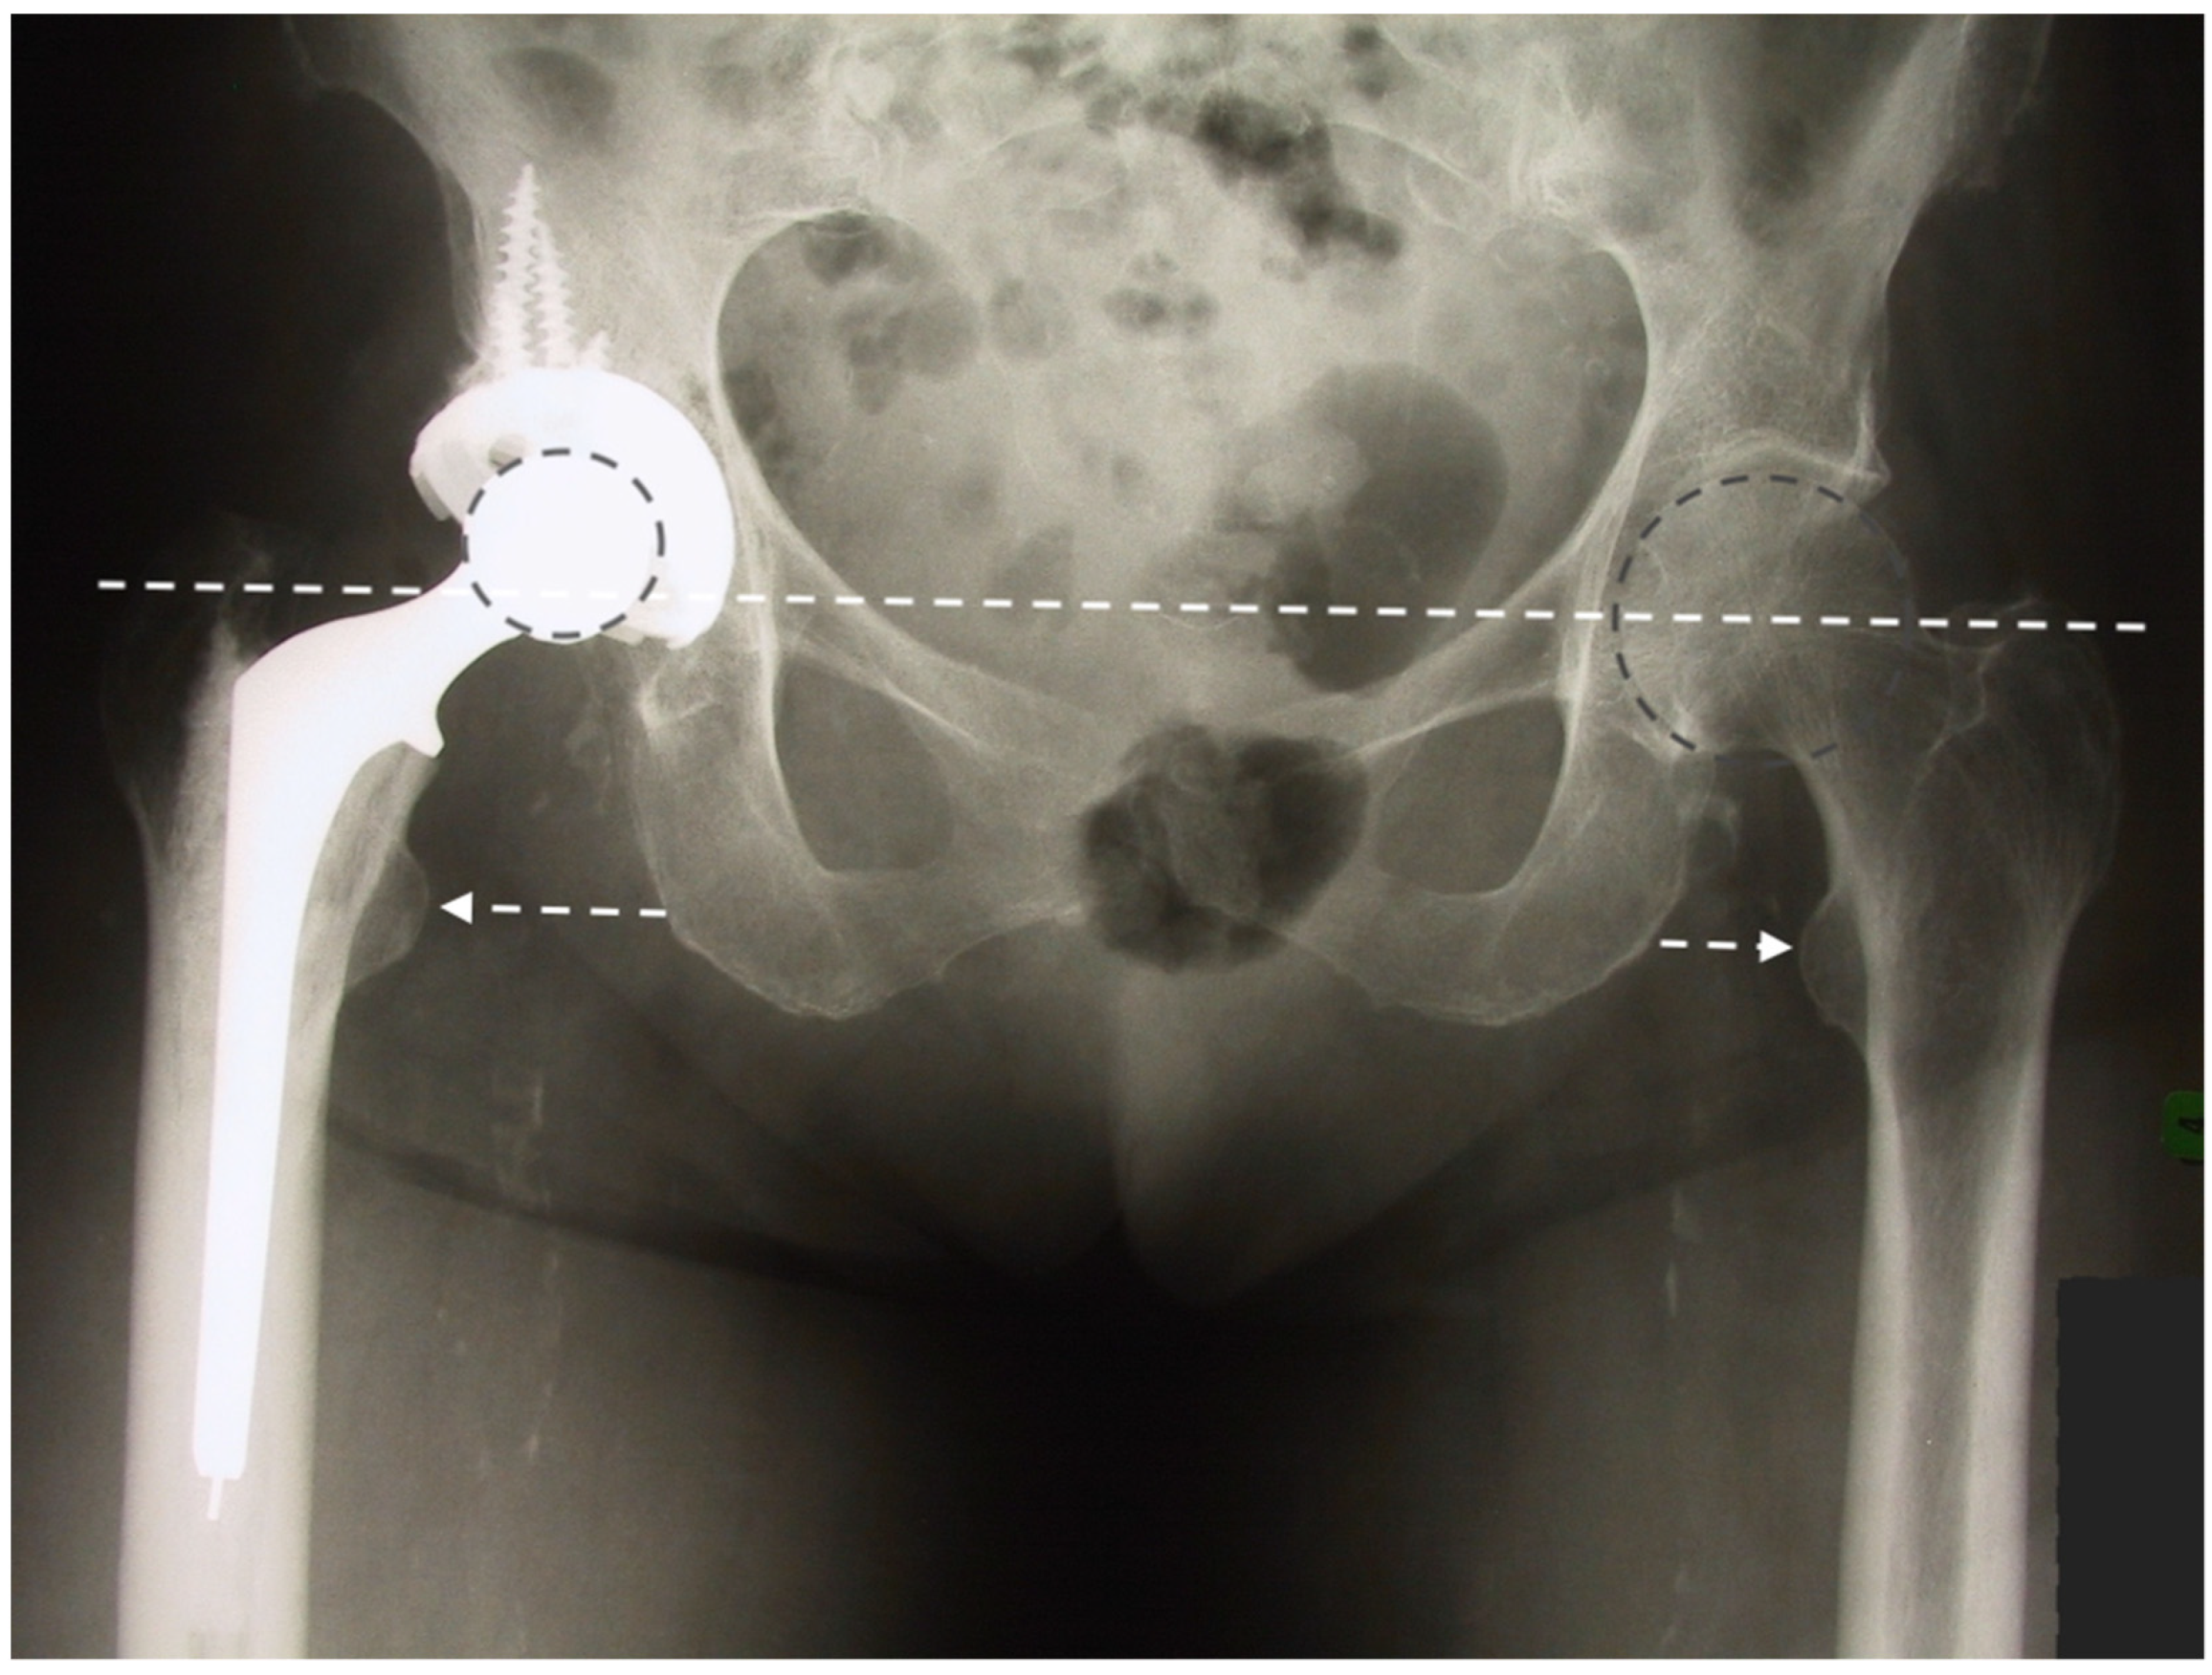

Precise biomechanical reconstruction of the hip by THA is essential for the success of this procedure. Optimal femoral offset and leg length restoration result in better abductor strength and clinical function. Failure to restore the normal anatomy for THA has been associated with a higher rate of dislocation, muscle weakness, limping, leg-length discrepancy, impingement, and early loosening of the implant (Figure 4) []. To improve the precision of the anatomic reconstruction, the range of sizes of the implant has been increased. Modular options have been introduced to give different neck-shaft angles and offsets of the stem. To enable the surgeon to achieve optimal restoration of the hip joint anatomy, different implant modularities, geometries, sizes, and computer navigation systems are now available.

Figure 4.

Anteroposterior pelvis radiograph of a patient complaining of right hip pain. Compared to his native left hip, the right 28 mm THA center of rotation was elevated, the femoral offset was increased, and leg length was shortened.

We prefer to use a fixed neck stem with three different neck angle options to better meet the different patients’ anatomies rather than a stem design with a unique angle and two different offsets (standard/lateralized). Less influenced by the risk of instability, surgeons using LDH THA can better optimize a patient’s leg length and femoral offset (Figure 5). In our experience and the literature, up to 10 mm of leg length difference can be tolerated; a shorter leg is much better tolerated than a longer one by patients []. In the cases where we hesitate between a shorter or a longer head (example: 0 mm vs. a +4 mm), we, therefore, select the shorter one.